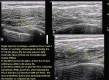

Figures